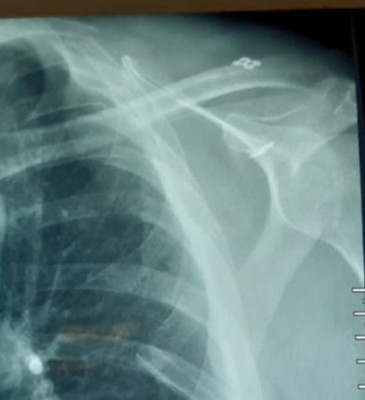

Reducido de luxación acromio clavicular con Dog Bone por arteoscopía de hombro

Envíado por Dr. José Israel Flores Hernández